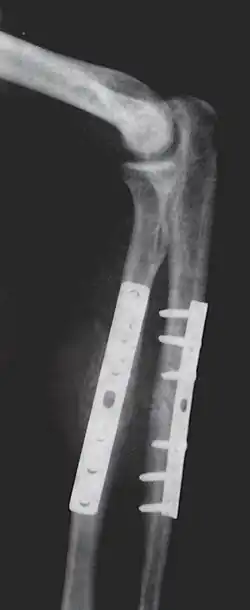

Orthopedic surgery or orthopedics (alternative spelling orthopaedics) is the branch of surgery concerned with conditions involving the musculoskeletal system.[1] Orthopedic surgeons use both surgical and nonsurgical means to treat musculoskeletal trauma, spine diseases, sports injuries, degenerative diseases, infections, tumors and congenital disorders.

- Repair fracture of radius/ulna